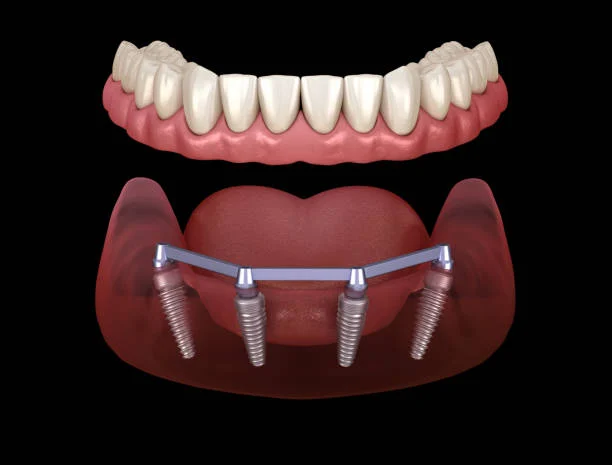

Dental Implant Surgery is a modern, permanent solution for replacing missing teeth using titanium implants that act as artificial tooth roots. These implants fuse naturally with the jawbone, providing exceptional stability and support for crowns, bridges, or dentures. The procedure restores full chewing ability, enhances smile aesthetics, prevents bone loss, and offers a long-lasting, natural-feeling replacement that looks, feels, and functions just like real teeth. With advanced techniques and precise planning, dental implants deliver reliable, comfortable, and life-changing results.